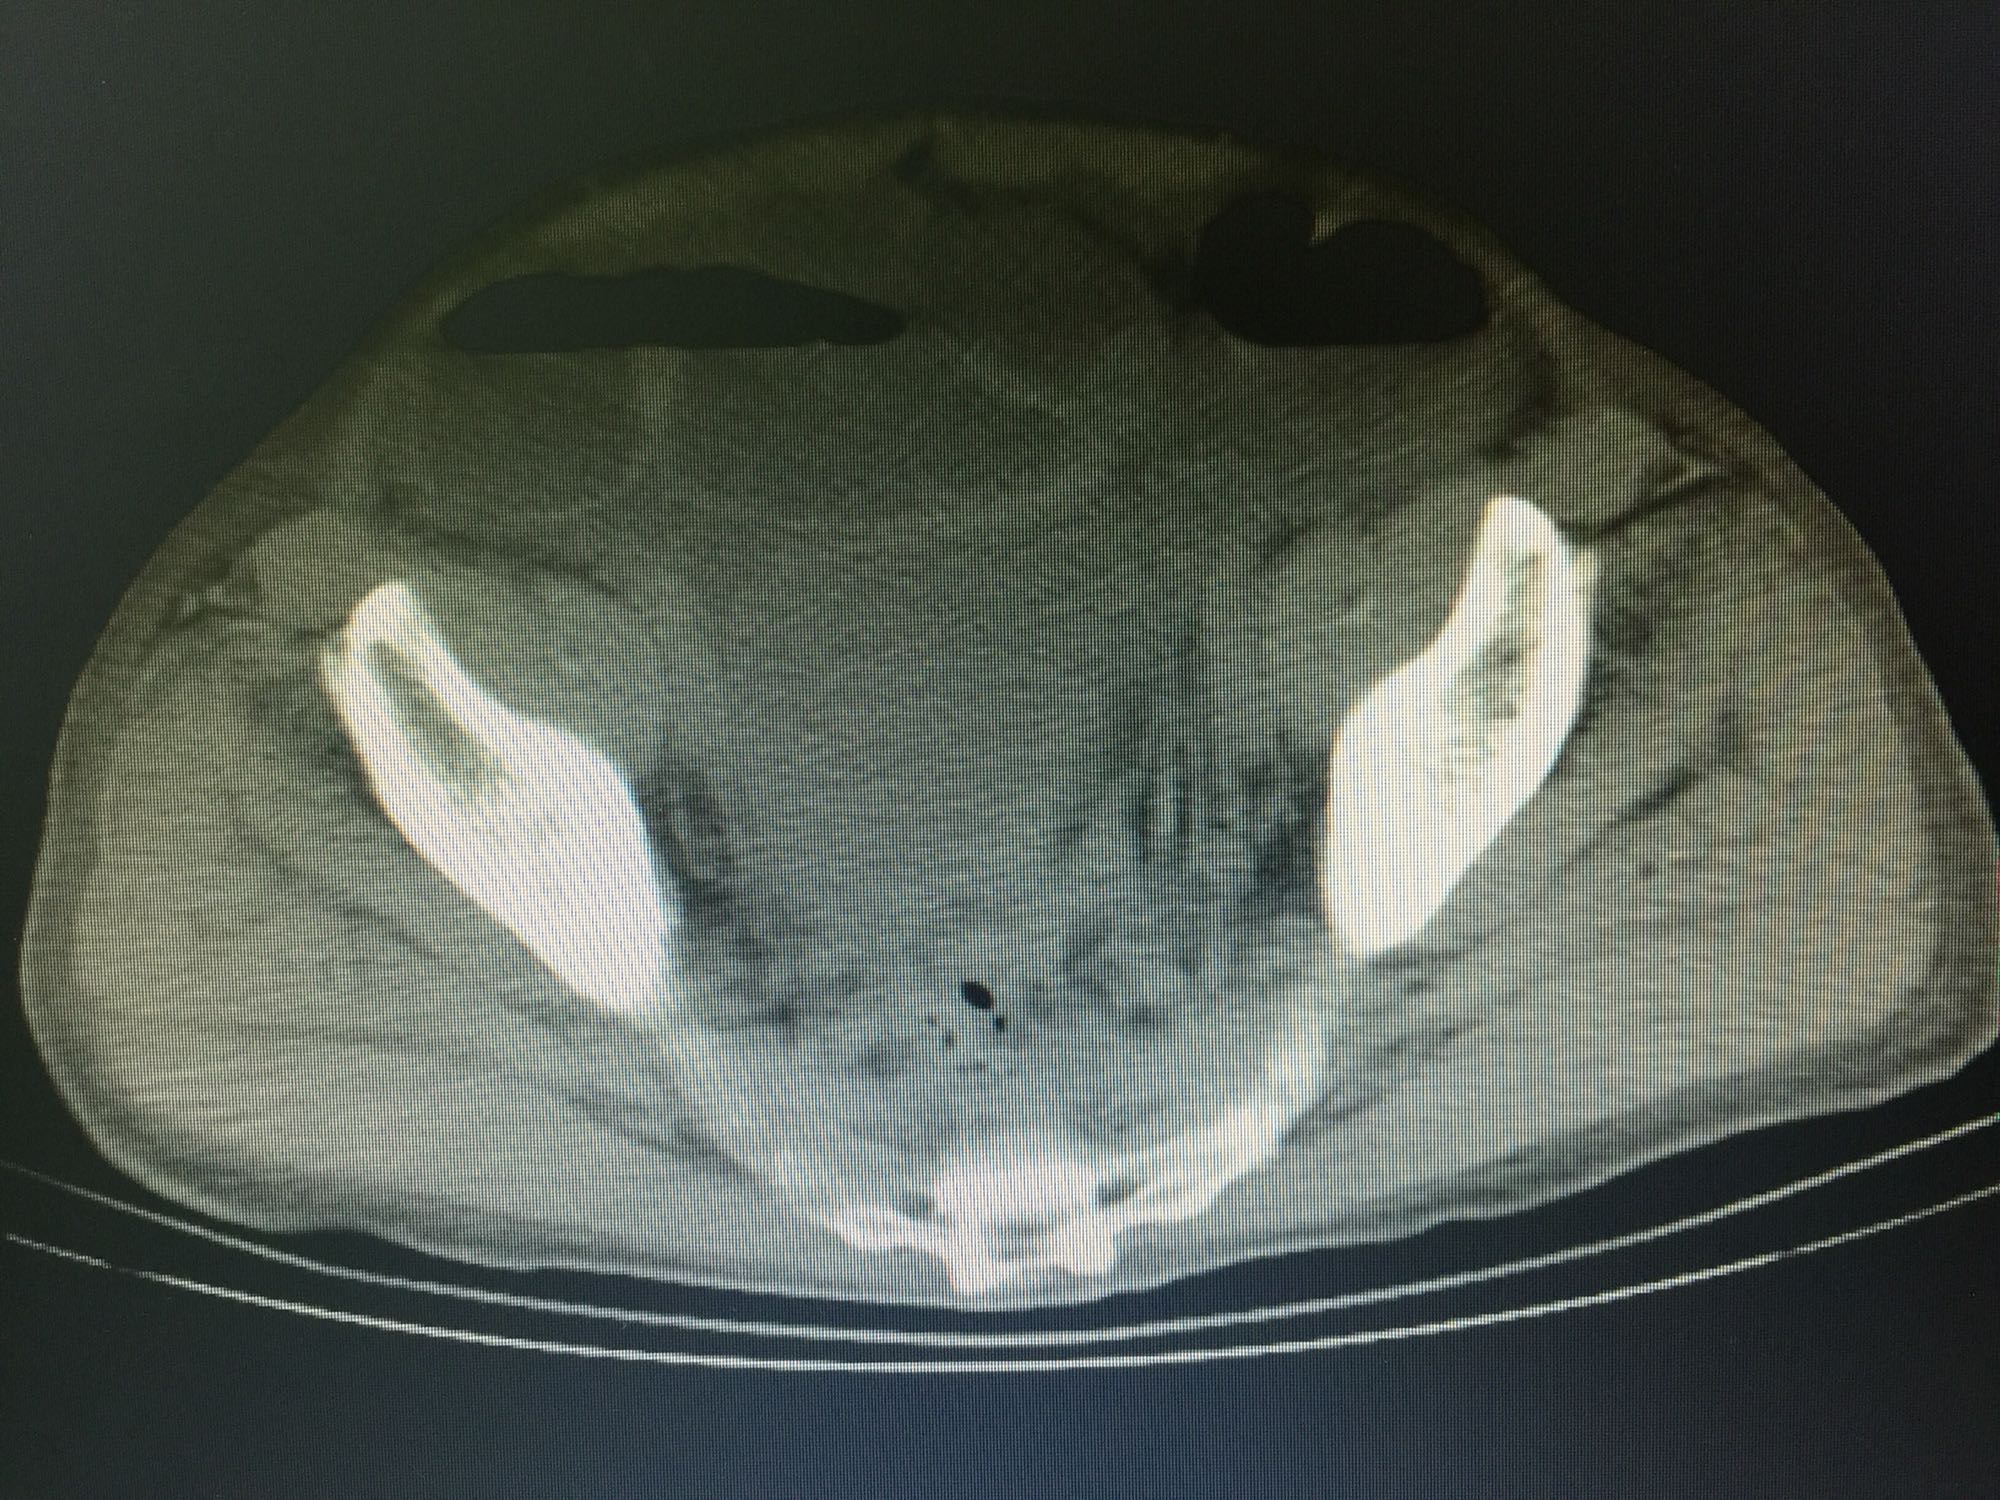

诊断:直肠癌,结肠息肉。 治疗:直肠低位前切除术,术后7天盆腔引流量逐渐增多,伴腹痛、发热,血像明显增高,腹部CT见腹腔大量积液,吻合口处结构不清晰,直肠旁间隙见条索状增强影;再次手术证实为吻合口漏。